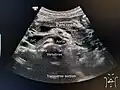

A normal pancreas on ultrasound.